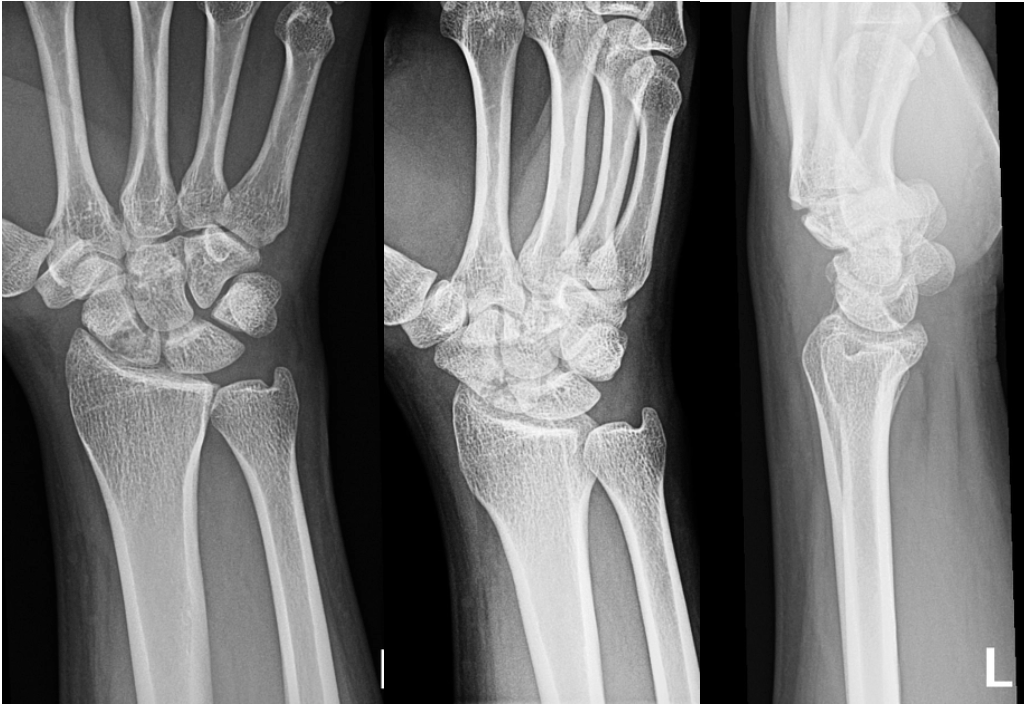

Scaphoid fracture WikEM What Is A Snuff Box Fracture It is the most common carpal bone to fracture among athletes, often caused by. This small bone is one of the eight carpal bones in the wrist. The anatomical snuffbox (also known as the radial fossa), is a triangular depression found on the lateral aspect of the dorsum of the hand. It is sometimes called a “snuffbox”. It is located. What Is A Snuff Box Fracture.

Snuffbox? Scaphoid fractures Radiology Key What Is A Snuff Box Fracture The anatomical snuffbox (also known as the radial fossa), is a triangular depression found on the lateral aspect of the dorsum of the hand. It is sometimes called a “snuffbox”. They happen when you break your scaphoid bone — a small bone near the base of. Anatomic snuffbox tenderness is a highly sensitive test for scaphoid fracture, whereas scaphoid compression. What Is A Snuff Box Fracture.